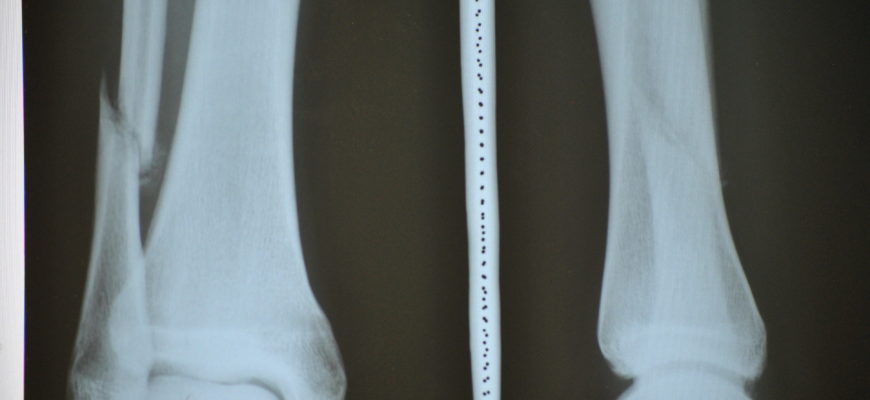

• Рентген в 2-х проекциях для уточнения характера травмы и ее типа (рекомендуется при закрытых переломах).

Перелом малой берцовой кости

Рентгенография — один из методов диагностики переломов малоберцовой кости.

В случае перелома головки малоберцовой кости врач назначает, помимо рентгена, МРТ или компьютерную томографию для уточнения повреждения сухожилий, связок и мышц. Рентген делают дважды: сразу после травмы и после наложения гипса, чтобы предотвратить неправильное сращение поврежденной кости.